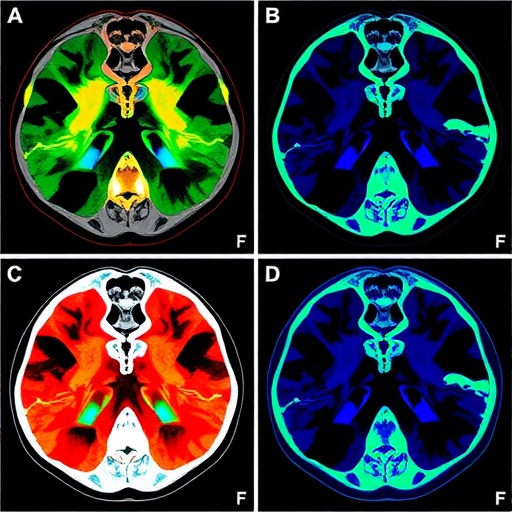

Hyperspectral imaging technology captures a wide spectrum of light from the sample, allowing for the detailed examination of tissue characteristics at a molecular level. Unlike conventional imaging techniques, hyperspectral imaging can analyze numerous wavelengths simultaneously, revealing subtle variations in chemical composition and cellular structure that are often imperceptible to the naked eye. The data generated from this technique is multidimensional, creating a rich dataset that requires advanced analytical methods for interpretation.

Moreover, the results demonstrated that the ANN could effectively classify histopathological samples based on their spectral signatures. This classification ability is paramount in differentiating between various grades of tumors and determining the appropriate therapeutic approach. The findings underscore the potential of hyperspectral imaging combined with machine learning as a revolutionary diagnostic tool, possibly transforming conventional biopsy techniques into more efficient and reliable processes.